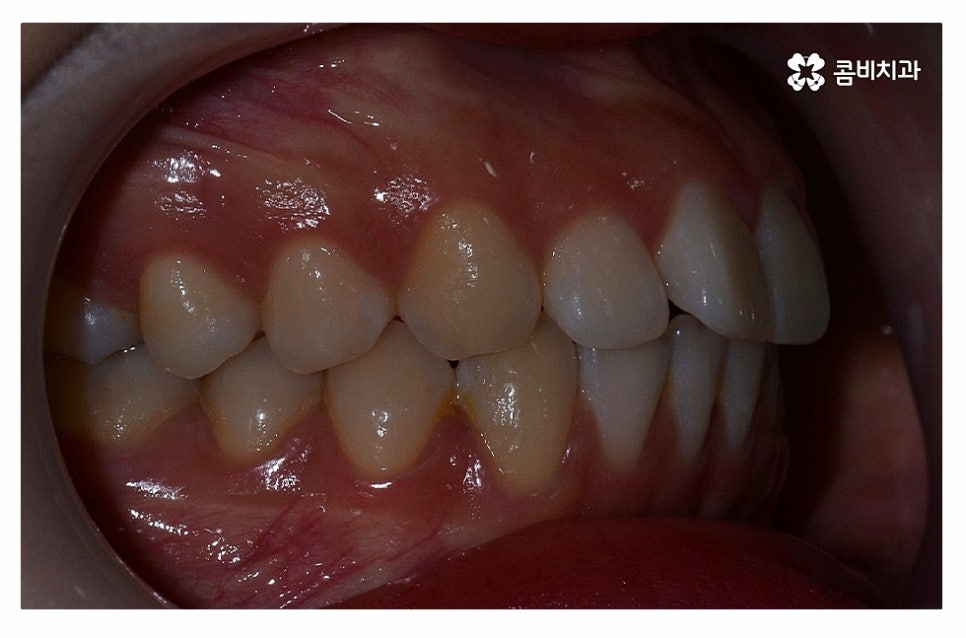

위 환자분의 경우 정면에서 보이는 치열은 가지런한 편이지만

치아가 돌출되어 돌출입으로 고민했던 사례이며

치아의 이동 공간 확보를 위해 발치 교정을 진행한 사례라고 할 수 있어요.

돌출입치아교정을 한다고 가정할 때 수술을 떠올리시는 분들도

많지만 비발치 혹은 발치를 통한 치아교정 만으로도

치료가 가능한 사례도 많기 때문에 정확한 진단이 중요하다고 할 수 있어요.